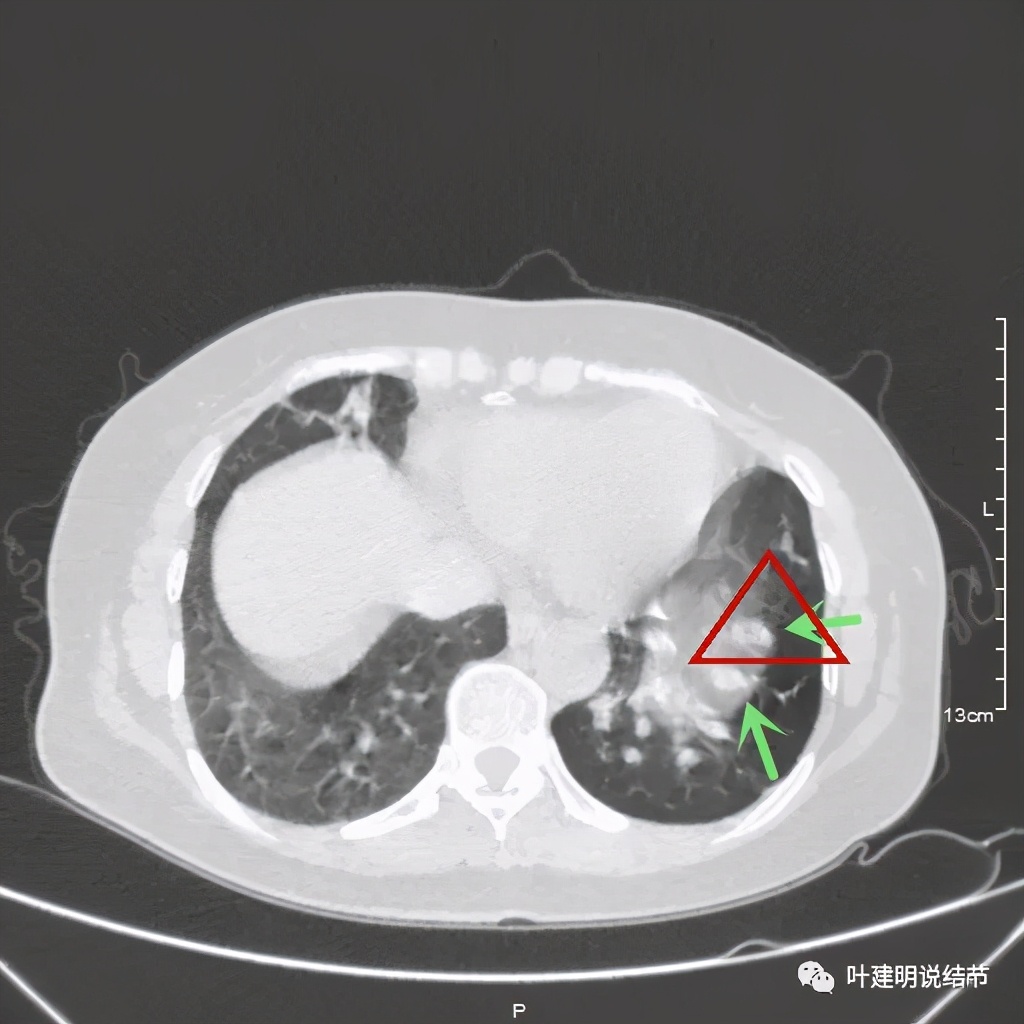

可见同样部位的左下结节已经较去年密度明显低了一些,说明有所吸收了!基本上已经只是磨玻璃密度了。那么其他病灶的情况呢?

也是有所变化,但病灶仍仍在,是异常的。最后这同图上还见到似乎也是实性伴小空腔的病灶(红色三角形标注处),是不是与之前的病灶有点像?

实性肺小结节的性质判断,一是看影像细节特征;二是看他处有没有类似病灶或病变;三是不太肯定是随访复查对比。这几点缺一不可,冒然过于积极手术,绝非最佳选择。网络问诊的病人的,经常有病友说,在某些大医院就诊咨询,大专家们经常会给似是而非的答案,告诉他们肺结节可能良性,也可能恶性,要病理化验才能确定。这样其实给病人仍是非常忐忑的心理负担,我们要用自己专业的判断,给他们尽量有倾向性的判断,帮助他们下决定随访抑或手术。我想,说清楚了,病人也会理解仅凭影像的判断达不到百分之百的。在避免过于积极干预的同时,也要避免耽误病情,而医生的不断努力能向更准确的术前诊断迈进!